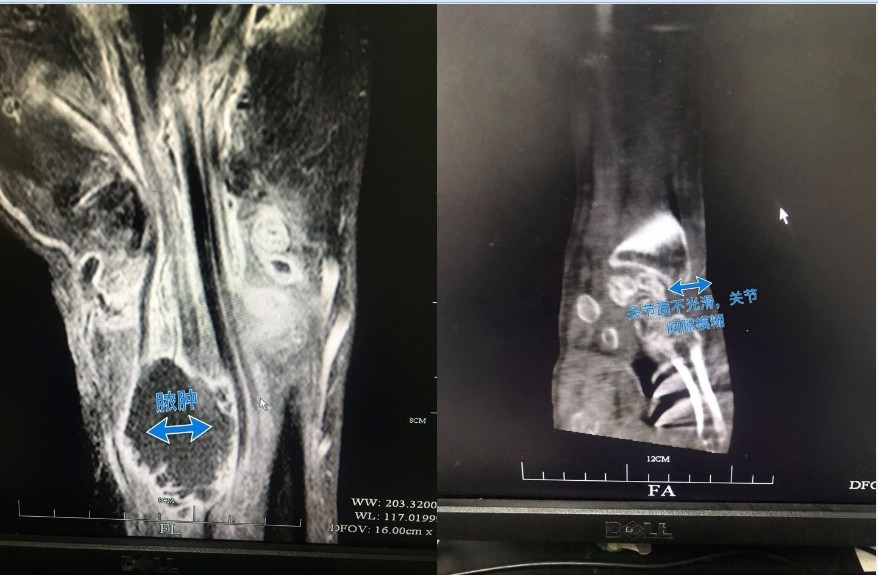

姚先生多次前往餘姚、寧波等醫院就診,都被診斷是「類風濕關節炎」,然而手腕潰爛流膿的依然沒有好轉,2016年年初又被診斷可能是「結核桿菌感染」,此時他的手腕潰爛情況已十分嚴重,甚至有要截肢的可能,最後前往浙江大學醫學院屬第一醫院求診,終於確診是遭「海分枝桿菌」感染。

醫生對症下藥後,姚先生的病症總算比較受到控制,但因為受傷時間拖太久,右手大量的肌肉、韌帶、神經已經爛穿,需要進行多次清創手術,醫生表示,「裡面爛掉的部位很多,光是清創就前後做了5次」,所幸總算保住右手,順利擺脫近3年的惡夢。